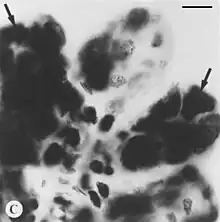

| Black and white Feulgen stained microphotograph depicting intact tick salivary glands infected by deer tick virus. Hypotrophied salivary acinus filled with amorphous masses of pinkstaining (=Feulgen positive) material (arrows). Scale bar = 10 µm. | |